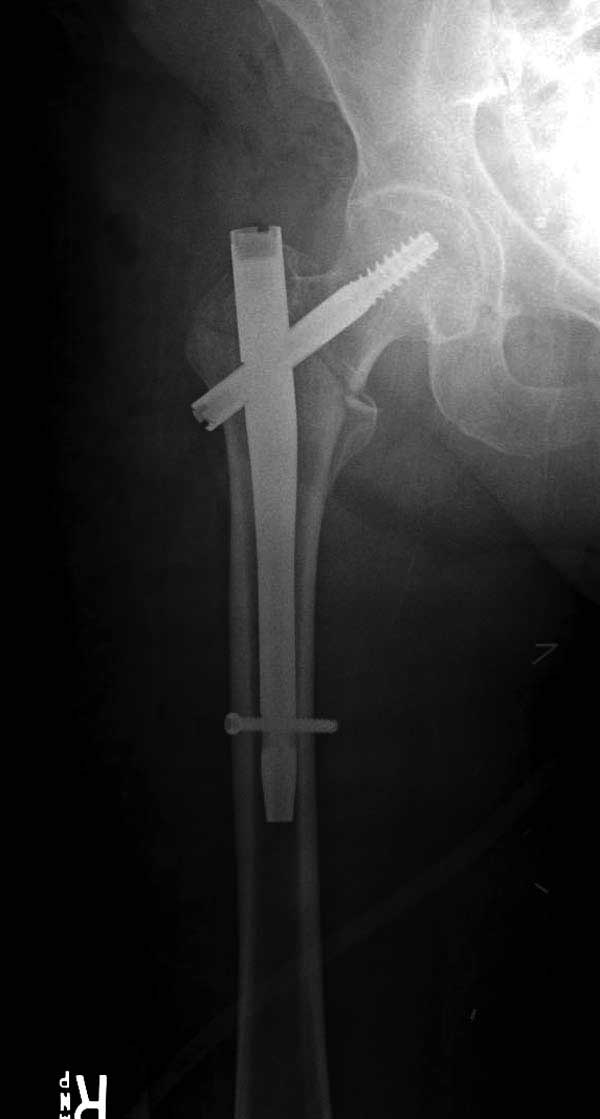

Банальный рутинный перелом чрезвертельной зоны лечимый DHS.

А по картинке можно сказать, что вроде бы все и неплохо. Предупредить миграцию шеечного винта при наружной ротации диафиза во время ходьбы достигают введением последнего поближе к переднему кортексу шейки. На Вашей картинке винт "смотрит" кзади. Отсутствие дополнительной боковой опоры для винта создает предпосылки для несостоятельности фиксации. (См. статью в прикреплении). Поэтому с ранней активизацией пациента в данном случае я бы подождал.

А пациент-то какой из себя?

При таком переломе мы бы тоже поставили вертельный гвоздь - на следующий день встать и побежать - чем не перспектива? На прямом снимке винт стоит замечательно, а коварный аксиальный подкачал, хотелось бы больше по центру шейки и головки завести. Да и смещение, какое-никакое, но есть. Посему - нагрузка 15 кг, а расширяли бы не раньше, чем через 5 недель.

Что касается данного перелома, то по-моему DHS или гамма - принципиальной разницы здесь конкретно нет - медиальная опора сохранена, при правильном исполнении можно ногу нагружать. Технически здесь выполнено на 3+, но если так же винт гаммы поставить - лучше не было бы.

Прилагаю снимок сделанный еще в стационаре через 2 недели после операции.

Первые снимки показывают технические погрешности установки DHS. Не была достигнута репозиция, конечность в флексии и шейка в ротации. Сегодня все меньше обращают внимание на параметры для оценки репозиции (S контуры Lowell в обеих проекциях и Garden Alignment Index, в норме 155 и 180 градусов), хотя такие простые тесты помогли бы дорепонировать смещение. Винт находится сзади в головке, что при нагрузке поменяет вектор и вместо компрессии в линии перелома срежет головку-Cut Out!

В зависимости от дистанции линии перелома и латерального кортекса надо использовать разной длины barrel, т.е. конец баррели не должен доходить до пределов перелома. Здесь конец длинного ствола упирается в медиальный фрагмент, что мешает созданию компрессии, а более короткий barrel создал бы запас для компрессии. В боковой пластине вместо 4х можно было ограничится двумя шурупами, потому что головка шурупа в 4.5 мм выдерживает давление до 350 кг.

В заключение: чрезвертельные переломы можно лечить разными методами, включая наружные фиксаторы, но для начала надо определиться, какой это перелом? Стабильные переломы А1 (1-3), А2 (1) можно фиксировать DHS или гвоздем, а нестабильные переломы - гвоздями или современными пластинами для проксимального бедра. Трудным считается Reverse obliquity A3 (1) который из-за скоса перелома лучше удерживает Blade Plate, но современные гвозди неплохо зарекомендовали в лечении таких переломов.